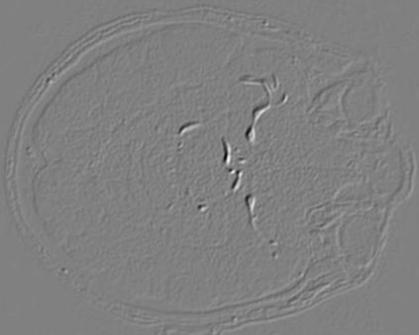

Figure 2 depicts the K=20 steerable filters of size . We also show sample filter responses to an MRA image to illustrate different characteristics highlighted by the steerable filters.